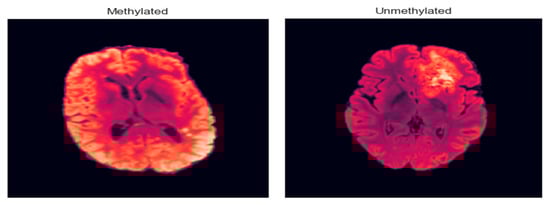

As illustrated in Figure 9, the model effectively distinguishes between representative MRI scans from unmethylated and methylated MGMT classes, demonstrating its capability to capture the imaging phenotypes associated with this critical genetic marker.

Figure 9. Methylated and unmethylated MGMT.